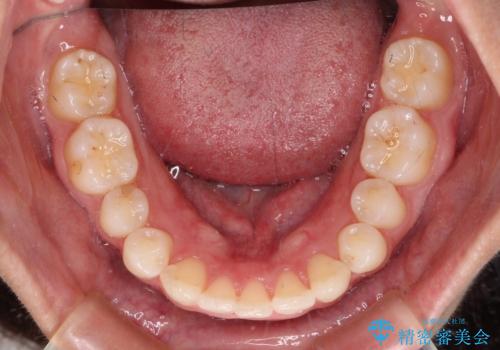

- 前歯の歯並びと神経を取って変色してしまった前歯を気にして来院された患者様です。

上下前歯の歯列不正はインビザラインにより整え、その後に、前歯2本をオールセラミッククラウンにて補綴治療することとしました。

下顎前歯が1本欠損しており、下顎歯列の大きさが本来よりも小さいため、上顎歯列とのバランスが悪く、深い咬み合わせになっていました。

上顎にIPRを多用して歯列の大きさを小さくするよう試みましたが、理想的な咬み合わせまでには改善させることはできませんでした。